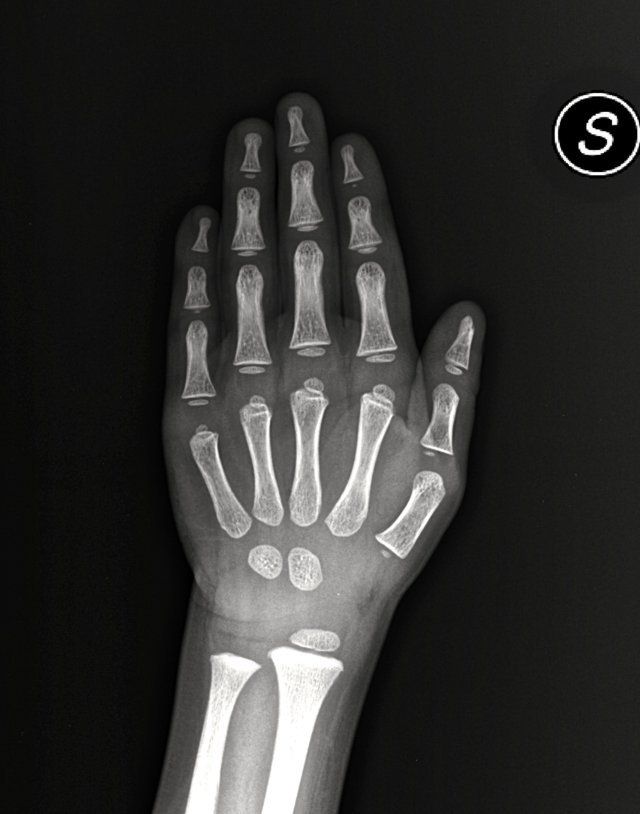

Nel Centro di Radiologia Muglia - Rago - Scaletta si eseguono tutti gli esami di routine dello scheletro, degli organi toraco-addominiali e gli esami contrastografici per lo studio della patologia intestinale ed in particolare la videofluorografia delle vie digestive superiori. La struttura si avvale di apparecchiature moderne e all’avanguardia, che ne fanno un innovativo centro di radiologia digitale a Bagheria e nei comuni limitrofi.

Il centro di radiologia è dotato di un sistema wireless per l'invio immediato delle immagini radiografiche ad un computer, mantenendo una qualità elevata ed evitando superflue esposizioni dei pazienti ai raggi X.

Tutte le immagini acquisite, trattate con un sofisticato post processing, vengono registrate su un supporto digitale (DVD).